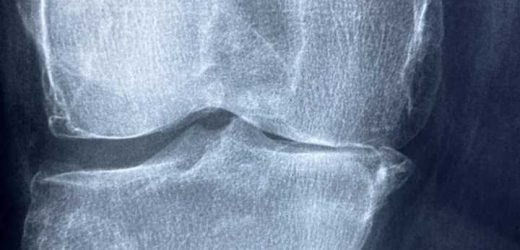

Read MoreChange in osteoarthritis care needed urgently, NZ health practitioners say

A group of New Zealand health practitioners is calling on the Government to change its approach to the way it cares for people with osteoarthritis, and to do so urgently. In an editorial published in the Journal of Primary Health…